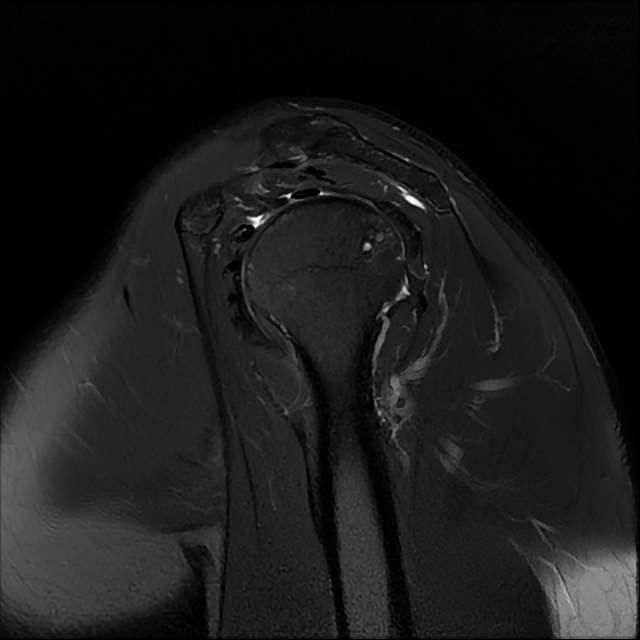

오른쪽 어깨 와순파열 및 점액낭염이 보인다고 하는데 상태를 알고 싶습니다

MRI 사진상 와순파열 점액낭염 등이 있다고 하는데..심한 상태인가요?

MRI상 와순파열, 회전근개 부분파열 등이 있으며 일부 염증소견이 있습니다.